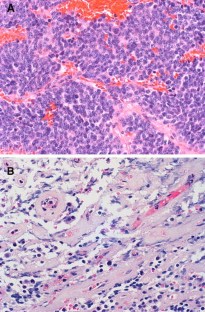

Fig. 1